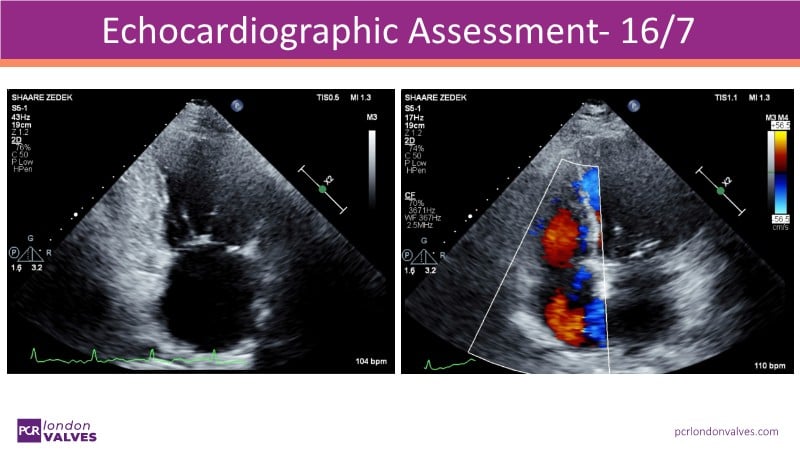

This LIVE case symposium brings mitral regurgitation guidelines into real clinical practice. Through step-by-step patient demonstrations and insightful discussion, the session explores how recommendations guide decision-making in ventricular and atrial secondary MR, how the heart team tailors therapy to individual anatomy and comorbidities, and how device iterations and procedural workflow can influence outcomes.